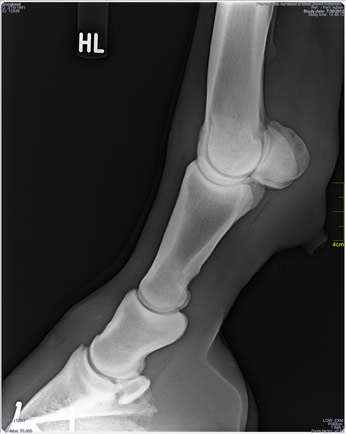

Dr. Millat (Pferdepraxis Aartalsee) diagnostizierte anhand vier digitaler Röntgenbilder:

"Gleichbeinlahmheit" und verordnete JANKID insgesamt 550 ml Hippopalazon und Cartilago Plus (Su: 400 Euro).

Außerdem empfahl uns Dr. Millat, ein Szintigramm in Telgte machen zu lassen, um eine seiner Meinung nach auch mögliche Ursache im Hankenbereich auszuschließen (ca. 800 Euro + Fahrt). Danach sollten dann zwei Tildren-Infusionen (à 500 Euro) in seiner Praxis folgen. Ein „Abspritzen“ (örtliche Betäubung der Gelenke) zur Eingrenzung des betroffenen Gelenks bzw. der betroffenen Muskulatur hat Dr. Millat nicht gemacht, garnicht in Erwägung gezogen.

Nach unserer Laien-Einschätzung liegt die Ursache "nach einem vermuteten Sturz auf panischer Flucht während eines Gewitters(?)" im linken Hankenbereich (Zerrung?, Gelenk/e?).

Nun widmet sich TAMME eigenhändig JANKIDs linker Hinterhand. Neben dem Bein, leicht dahinter stehend, hebt er es an, mit der linken Hand von vorn an der Hinterröhre und der rechten von hinten auf dem Sprunggelenk. Nach ein paar erkundenden, sondierenden (wonach?) Bewegungen streckt er das lädierte Bein JANKIDs nach hinten außen.

Elke: "JANKIDs ausdrucksstarke 'Kamel-Mimik' bei dieser Aktion spricht Bände - wie den Fotos zu entnehmen ist, wohl auch meine eigene. Als habe man ihm eine volle Ladung Pfeffer in die Nüstern geblasen: Das hat ihm offensichtlich weh getan, und er traut sich auch erst einmal nicht, sich wieder auf sein linkes Hinterbein zu stellen."

TAMME: "Er hat sich wohl gespreizt (einen Spagat gemacht?) und dabei gezerrt. Zusätzlich ist dabei wohl Abrieb von den altersbedingt arthritischen Gelenken angefallen, der nun erst “verrieben” werden muss. Das tut ihm natürlich weh. Ich schätze, dass JANKID wohl noch den ganzen Sommer brauchen wird, bis das wieder völlig o.k. ist."